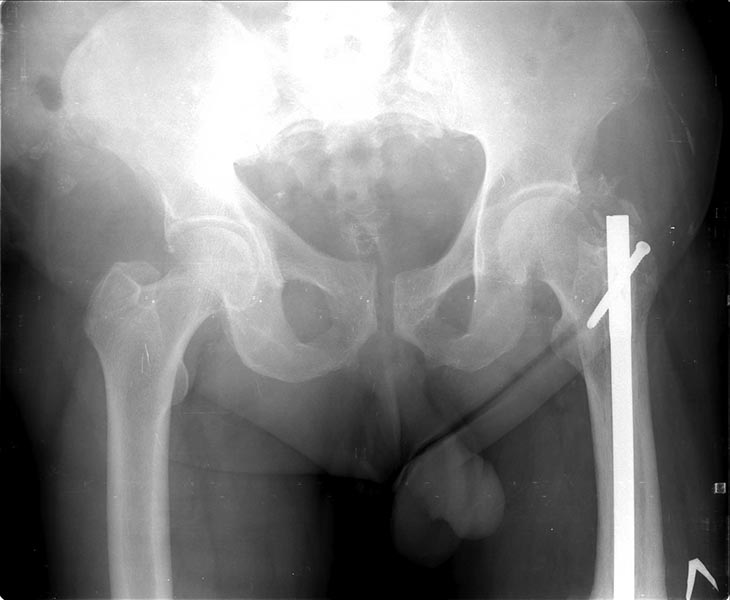

Коротко о пациенте: Возраст 60 лет, мужчина. Со слов травма в 2006

года-ДТП (сбит автомашиной) - в январе 2007 г. выполнено БИОС левого

бедра , затем по неизвестным причинам в 2008 году реостеосинтез левого

бедра штифтом ( снимков нет). Оперирован в одном из городов Сибири.

На снимках( это снимки январь 2015г), которые выложил, определяется

гипертрофический ложный сустав с/3 бедренной кости, перелом штифта на

уровне перелома, штифт канюлированный.Состояние больного